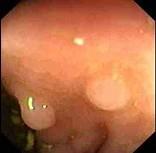

男性,46岁,有结肠癌家族史,行肠镜检查如图,诊断为 ( )A.直肠癌B.直肠炎性息肉C.直肠腺瘤样息肉D.直肠绒毛样息肉E.克罗恩病

问题 男性,46岁,有结肠癌家族史,行肠镜检查如图,诊断为 ( )

选项 A.直肠癌 B.直肠炎性息肉 C.直肠腺瘤样息肉 D.直肠绒毛样息肉 E.克罗恩病

答案 B